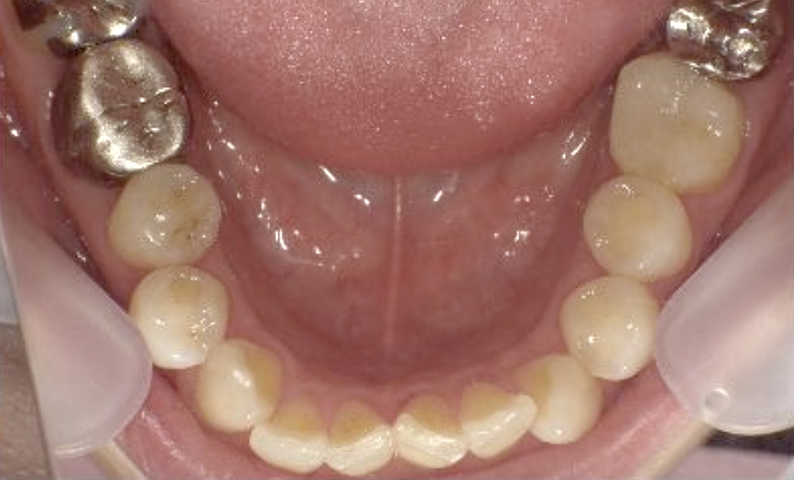

症例_001 下顎だけの部分矯正

治療期間:8ヶ月金額:21万円+税女性前歯のガタガタ下の前歯だけ

| Before | After |

|---|---|

|